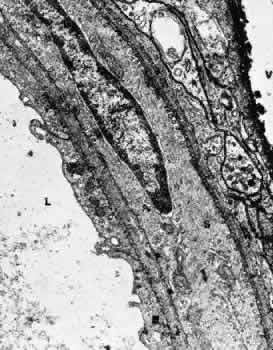

Retinal arterioles are similar to the arteries except that the lumen is small (8 to 15 μm in diameter), the media contains one or two layers of circularly or obliquely arranged smooth muscle cells, and the adventitia is poorly developed and consists of the outermost layer of basement membrane surrounding the smooth muscle cells and small amounts of collagen fibrils (Fig. 4).15

Fig. 4. Electron micrograph of a human retinal arteriole from the nerve fiber layer. This specimen was treated with ruthenium red. E, endothelial cell; S, smooth muscle cell; L, lumen; V, vitreous.